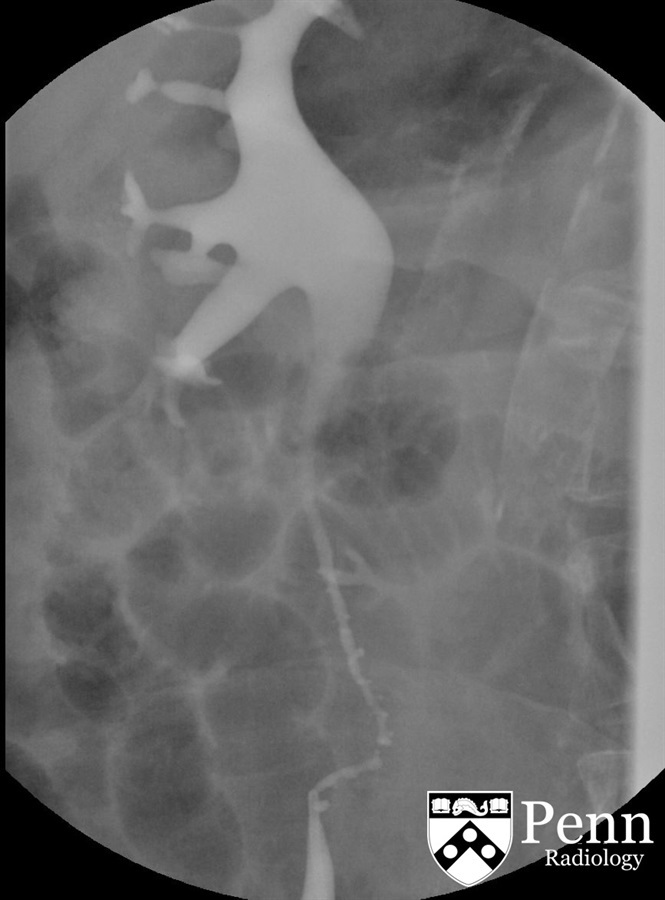

ureteral pseudodiverticulosis

multiple ureteral outpouchings that are smaller than 5 mm

most common location of ureteral pseudodiverticulosis

bilateral, upper 2/3 of ureter